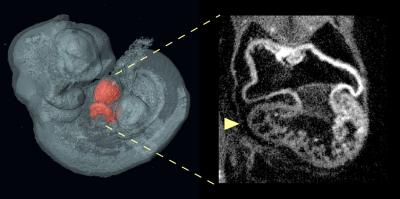

3-D Embryo

image: Optical projection tomography of an E10.5 Nipbl+/- mouse embryo shows, on the left, a three-dimensional reconstruction of the embryo with heart highlighted in red; on the right is an optical section through the heart showing an abnormally small right ventricle. view more

Credit: Benedikt Hallgrimsson/University of Calgary